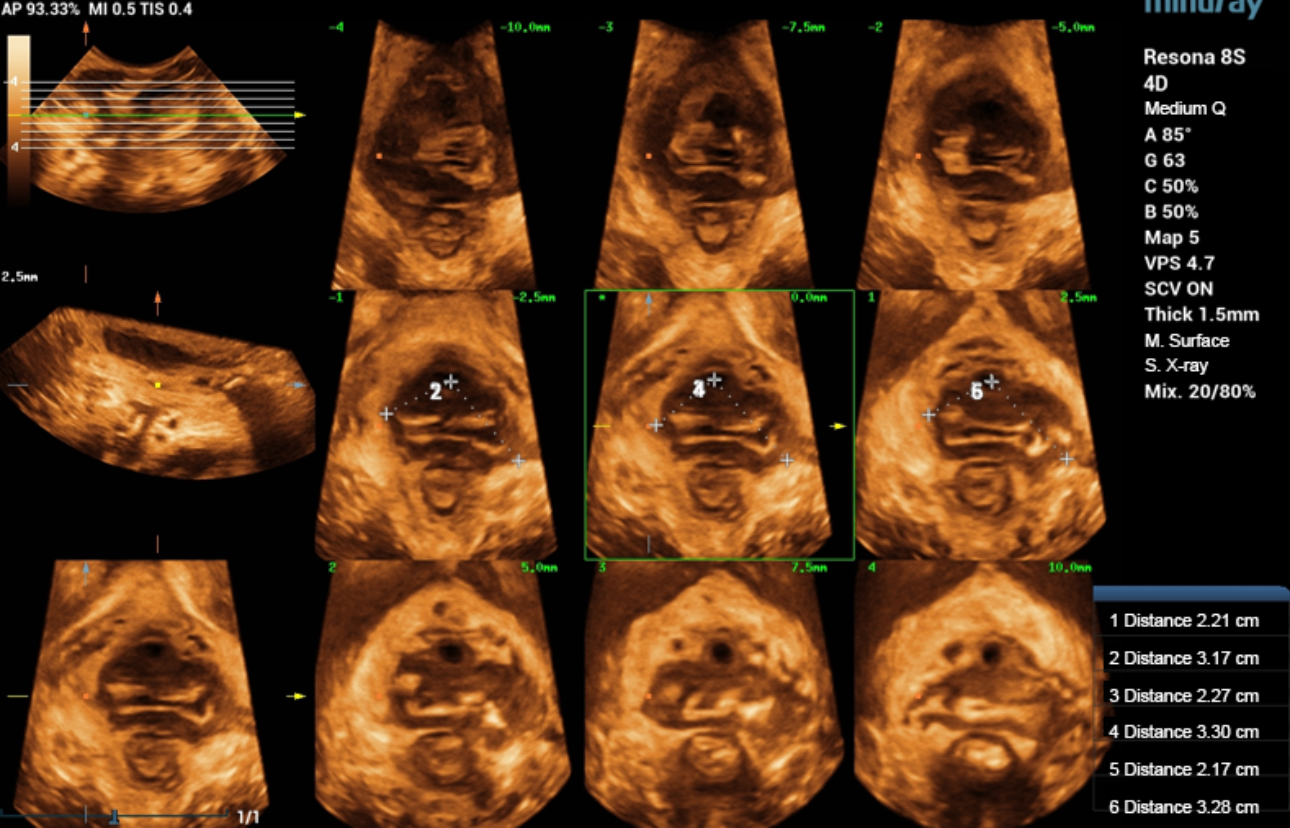

?? ?? ????? parasagittal view??? ???/?? 2D ???, 3D/4D ?? ??, Ipage+?? ?? ?? ?? ???? ?????.

?? 39??? 30???(G1P1)?? ??? Negative-pressure vacuum extraction? left perineotomy? ?????, ???? ???? 3.387kg?????. Pelvic floor ???? ?? 42? ? ???????.

- 2D ?? : ???? ??? ?? ?? ???? interruption? ?? ???? ??? ?? ??? ??.

- Levator hiatus? ?????? ?? ????? ?? ??.

- Ipage+ : ? ? ??? slice?? ?? ?? ?? levator avulsion? ?? ??, levator trauma ??? ??? ? ? ??.